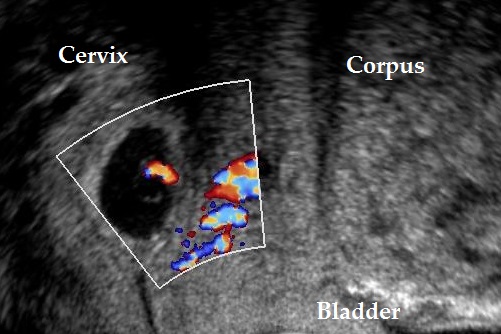

Visualize the ectopic pregnancy.